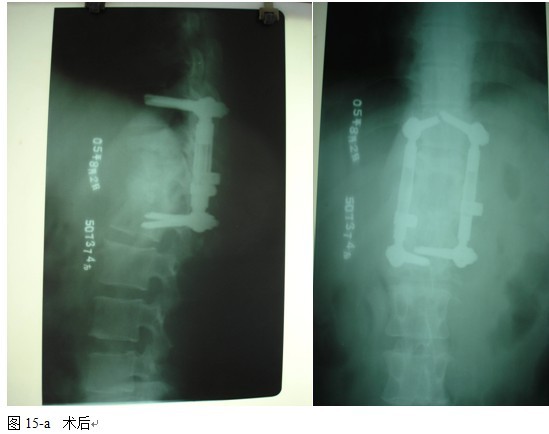

2.2 手术方法

全麻后气管插管,俯卧位,根据术前影像学分析确定需显露的椎体数目。

以病变椎体为中心,作一后正中切口,显露病椎棘突、椎板、关节突以及上下需要固定的正常椎体,根据后凸畸形的严重程度在C 型臂协助下确定进钉角度和方向,置入椎弓根钉,椎弓根钉固定的方法:病灶上下相邻正常椎体置入,当病椎骨质破坏不超过1/3或未累计椎弓根时置入相对较短的钉子,一般长度为35mm,当骶1椎体有破坏时,根据骨质的情况确定入钉的方向,将病椎上、下关节突关节切除,自椎间孔显露病灶,直视神经根状态下进行病灶清除和椎管减压,可将干酪样物,死骨,坏死的椎间盘大部分清除,解除硬膜囊的压迫,必要者可双侧同时病灶清除,减压。无钛棒状态下用椎体撑开器轻柔牵开,采用前路撑开结合后路固定维持有限撑开或加压缓慢矫正脊柱后凸畸形,特别注意是由于结核患者骨质疏松,不可用钉棒大力撑开,否则钉子拔出可能性较大。要前路撑开加后路加压来达到矫形的目的。撑开后,缺损空间增大,大部分用手指可触及缺损内的情况,能进一步彻底清除病灶及对侧的病灶,反复用异烟肼盐水混合液冲洗病灶,凿出植骨床,植骨时需注意植骨块要采用“平进竖植”方法,循序用植骨打入器和辅助器械缓慢植入否则易导致神经根损害。植骨完成后再次采用内固定适当加压促使骨块稳定及融合,如果病灶中的脓液稀薄较多时,在病灶中留置一根硬膜外管,术后注射异烟肼,每周两次,以提高局部的药物浓度,在对侧椎板,关节突间植骨,病灶内留置链霉素2.0g ,放置引流管,闭合伤口。

本组手术用时间3~4h , 平均3.5h 。术中出血300~500ml , 平均约350ml 。术后症状完全缓解,无神经功能障碍加重等并发症,1例营养差的老年患者伤口出现窦道,1例因肝功能差,术后未口服抗痨药,伤口出现窦道,经换药后二期愈合,其余病例伤口均一期愈合。马尾神经受损的患者术后基本恢复正常。术后一周后凸角平均 5.4°后凸畸形平均矫正90%以上, 最终后凸角平均8.3°,后凸角度平均丢失4.2°。随访3个月有87%(40/46)有骨痂形成,6个月91.3%(42/46)明显骨性愈合(见图),其余4例9-12个月内愈合,随访时间3-32个月,平均11个月,46例患者中2例在术后2个月和3个月时背部形成脓肿,换药后治愈。2例出院1月后并发结核性脑膜炎,治疗后好转。1例因椎弓根钉偏外,刺激神经根,5个月后从侧方脱出,疼痛加重,因前后路植骨完全愈合,取出后症状完全缓解。